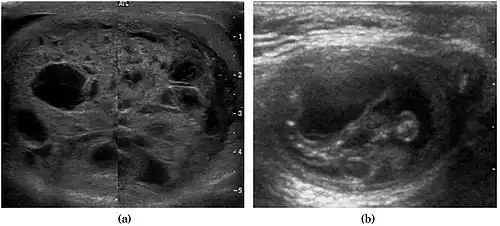

Teratoma Although teratoma is the second most common testicular tumor in children, it affects all age groups. Mature teratoma in children is often benign, but teratoma in adults, regardless of age, should be considered malignant. Teratomas are composed of all three germ cell layers, i.e. endoderm, mesoderm and ectoderm. At ultrasound, teratomas generally form well-circumscribed complex masses. Echogenic foci representing calcification, cartilage, immature bone and fibrosis are commonly seen [Fig. 5]. Cysts are also a common feature and depending on the contents of the cysts i.e. serous, mucoid or keratinous fluid, it may present as anechoic or complex structure [Fig. 6].

![Fig. 6. Mature cystic teratoma. (a) Composite Image. Mature cystic teratoma in a 29-year-old man. Longitudinal sonography image of the right testis shows a multilocular cystic mass. (b) Mature cystic teratoma in a 6-year-old boy. Longitudinal sonography of the right testis shows a cystic mass containing calcification with no obvious acoustic shadow.[citation needed]](./_assets_/Ultrasonographies_of_mature_cystic_teratomas.jpg) Fig. 6. Mature cystic teratoma. (a) Composite Image. Mature cystic teratoma in a 29-year-old man. Longitudinal sonography image of the right testis shows a multilocular cystic mass. (b) Mature cystic teratoma in a 6-year-old boy. Longitudinal sonography of the right testis shows a cystic mass containing calcification with no obvious acoustic shadow. Fig. 6. Mature cystic teratoma. (a) Composite Image. Mature cystic teratoma in a 29-year-old man. Longitudinal sonography image of the right testis shows a multilocular cystic mass. (b) Mature cystic teratoma in a 6-year-old boy. Longitudinal sonography of the right testis shows a cystic mass containing calcification with no obvious acoustic shadow.